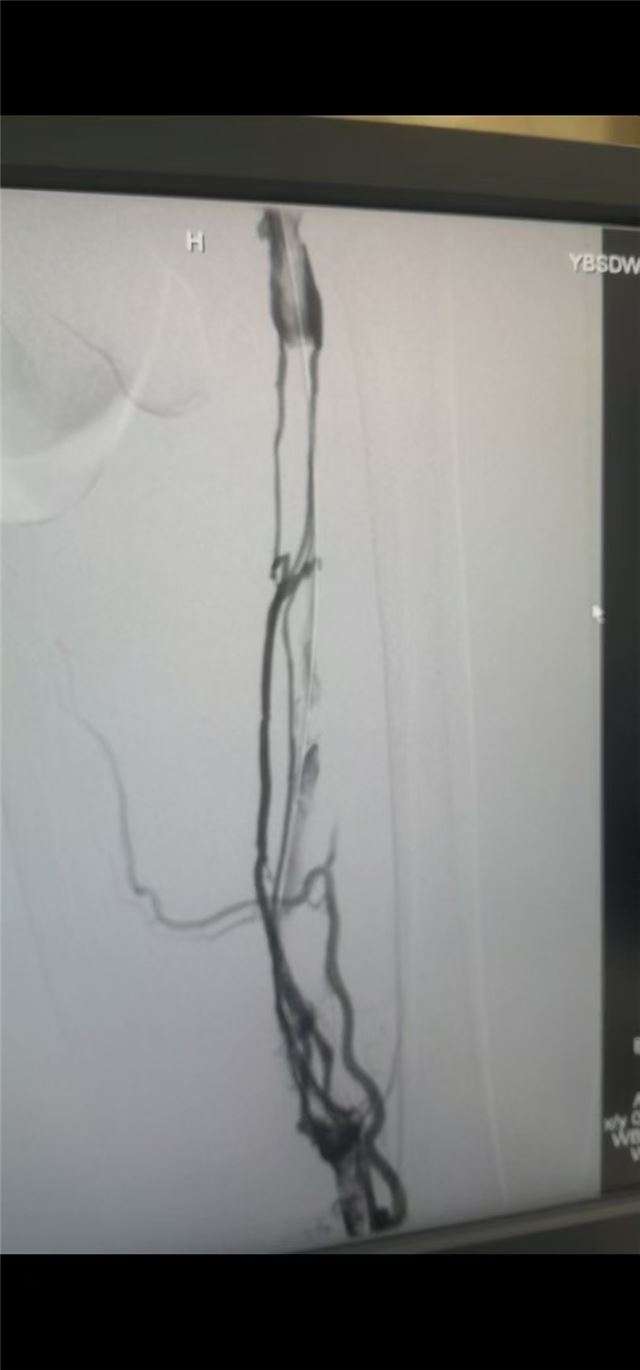

手术前下肢深静脉造影

下肢深静脉血栓是一种起病急、危害大的血管疾病,若治疗不及时,极易引发患肢肿胀、疼痛、功能障碍,严重时血栓脱落可导致肺动脉栓塞,危及患者生命。传统治疗以抗凝、溶栓药物保守治疗为主,存在治疗周期长、血栓清除不彻底、后遗症发生率较高等局限性。

为更好地满足患者诊疗需求,该院胸外普外二科血管技术组团队紧跟医学前沿,经过充分的术前调研、技术论证和专业培训,率先引入下肢深静脉血栓介入治疗技术。该技术在数字减影血管造影(DSA)精准引导下,通过微创穿刺建立通路,采用导管溶栓、机械血栓清除、球囊扩张成形、支架植入等个性化介入手段,可直接作用于血栓部位,实现血栓的快速清除和血管的通畅重建。